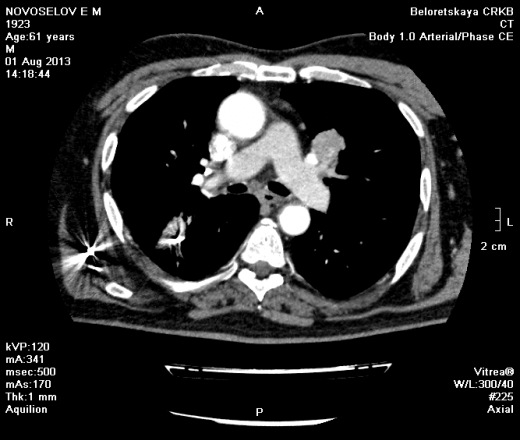

Мужчина оперирован по поводу BL щитовидной железы.Неоднократно проходил КТ в других лечебных учреждениях, у нас- впервые.Ставились заключения:MTS в лёгкие и лимф.узлы средостения слева.Образование слева увеличилось.Жалуется на одышку, не верит в заключение о MTS,просит узнать мнение других специалистов.

Отправляю ссылку на Яндекс-диск.Забыл ещё добавить,что у пациента давно было ранение дробью справа(артефакты от металла)

Метастазов в легкие не вижу. Похоже на лимфоузел в головке левого корня. Если позволите, запаздываете с началом исследования, плотность контраста в легочных артериях должна быть выше, чем а аорте. А одышка, не мудрено, легочная ткань диффузно уплотнена по типу "матового стекла", написал бы какую-нибудь интестициальную пневмонию, по типу альвеолита, может быть и гиперчуствительный пневмонит (не разберу есть или нет внутридольковые очажки), посмотреть бы изначально легочное окно, а не восстановленное из мягкотканного.

Кажется,я понял,что Вы имели ввиду.Очажки стрелочкой указал.Согласен с тем,что очаги на фоне отображеничя сосудов кажутся фантазией,но они присутствуют.

Коллега, вынужден извинться и дезавуировать свой первый пост. Пересмотрел. Да, есть очаги, и они - вероятнее всего, метастазы.

Думаю, да. Слишком близко лежит к легочной артерии.